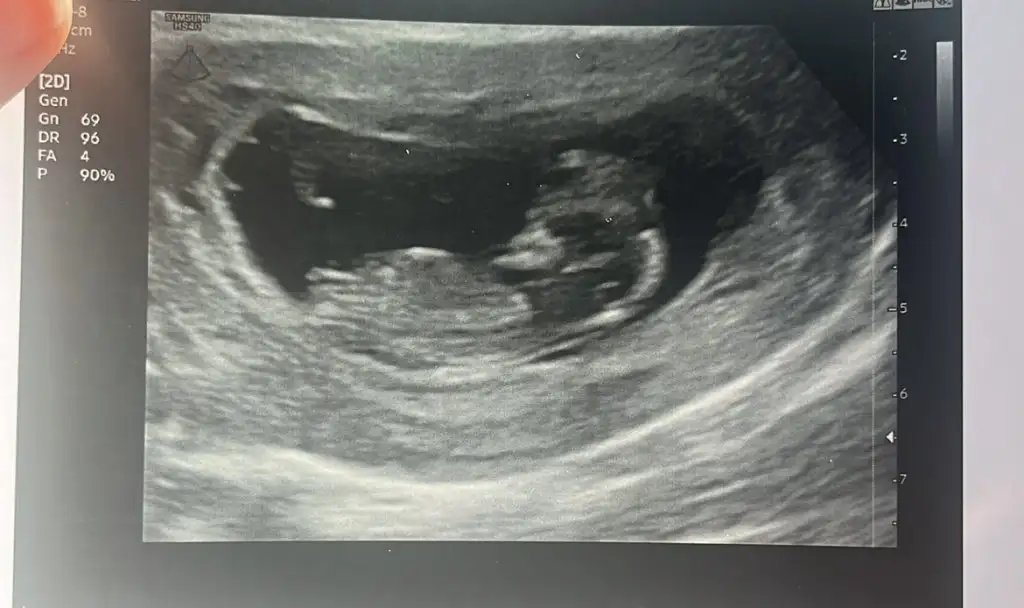

ErkekKizlar meraba nasilsiniz cok sukur 15+4haftalik olduk dr bir tahminde bulundu ama kesin demedi acaba degisirmi siz de yorumlarsaniz sevinirim

Kız gibi sankiKizlar meraba nasilsiniz cok sukur 15+4haftalik olduk dr bir tahminde bulundu ama kesin demedi acaba degisirmi siz de yorumlarsaniz sevinirim

Malesef kiz tahmin ediyorum dedierkek mi seninki

Kız gibi sanki

hiç net değilki bakalım